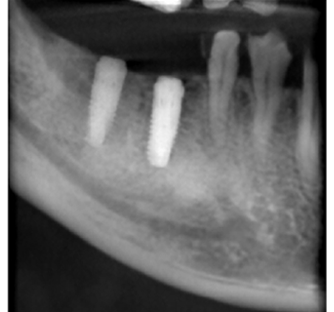

上記は歯のレントゲン写真です。二本足のように、歯が歯茎に埋まってますが、右の歯の黒い部分(二本足のつけ根の部分)が菌に冒されてます。

-

非常に細かい部分ですが、顕微鏡を使い、菌に犯されているところを治療した後にレントゲンを取りました。

しっかり治ってます!!